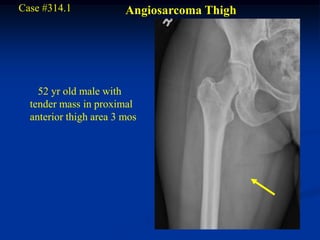

Case #314.1             Angiosarcoma Thigh

52 yr old male with

tender mass in proximal

anterior thigh area 3 mos